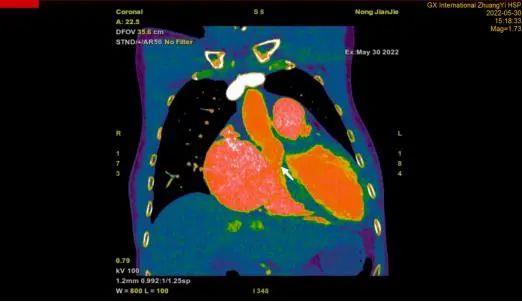

CTA检查:箭头所指为主动脉窦瘤破裂至右心的异常通道